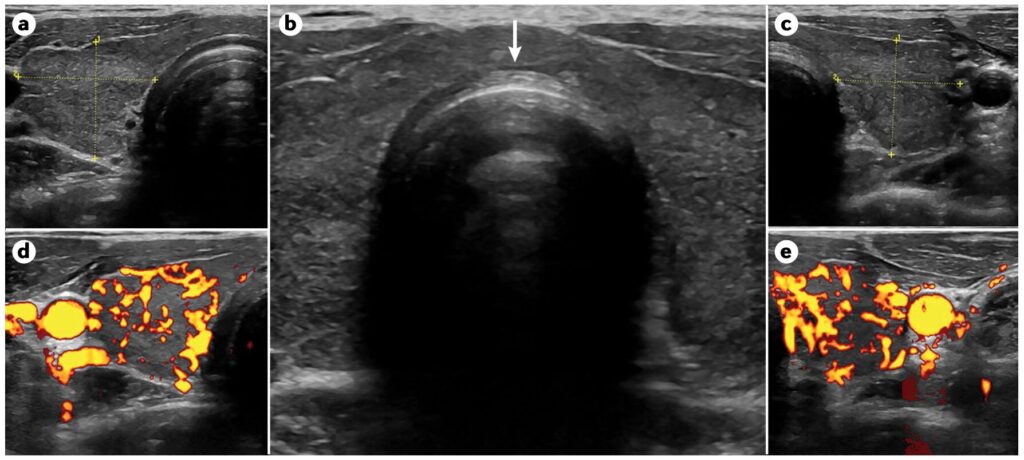

甲状腺エコー

上記の図はバセドウ病に典型的な、甲状腺腫大の例です。ドップラー超音波検査による甲状腺葉(左葉(cとe)と右葉(aとd))の画像で、バセドウ病の甲状腺の血管を示すカラー表示の有無と、中央部(b)に太い峡部(矢印で示す)がはっきり見えます。